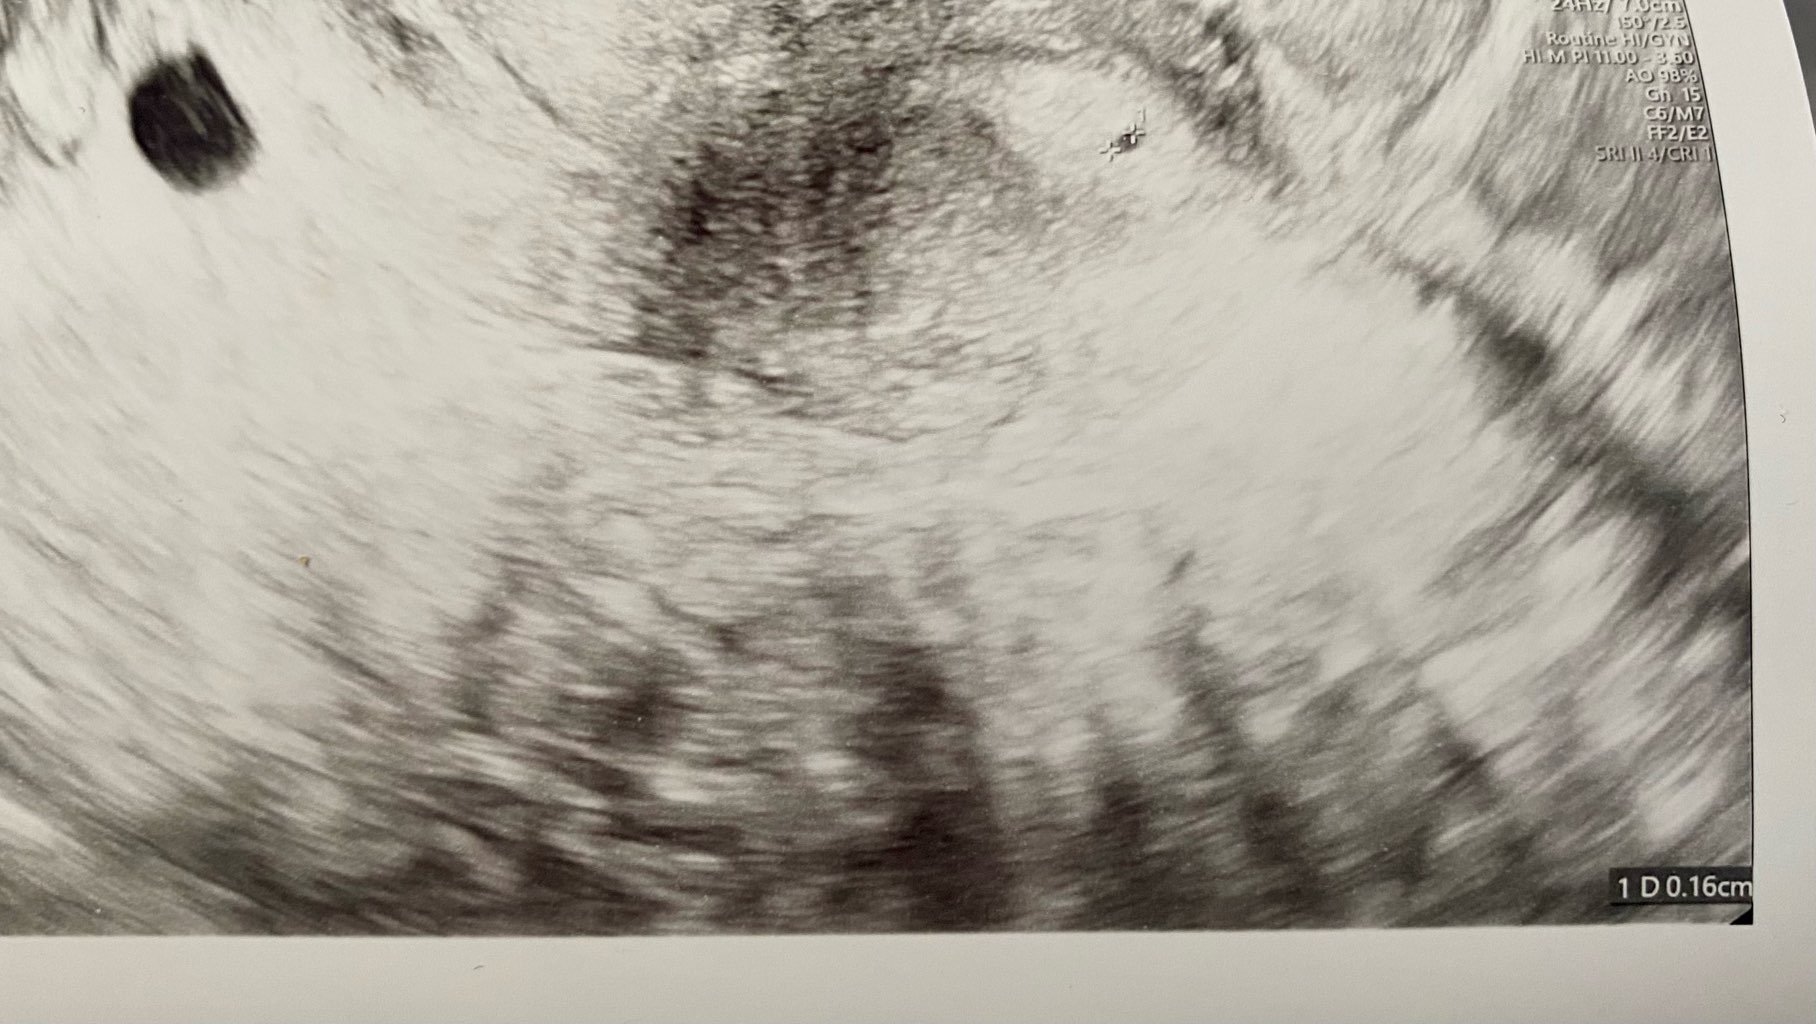

No u mnie w okolicy to na koniec grudnia dopiero termin.. Nie będę jechała dlaej o 100km na usg, bo w 6 może być tylko pęcherzyk, a ja chce serduszko zobaczyć. Więc akurat u mnie będzie 7t4d jak będę na wizycie. Więc spokojnie już będzie widać.. Ostatnia ciaza zatrzymała mi się w 8t3d także będę pewnie po usg żyła w stresie.. I pewnie szybko pójdę na kolejną wizytę..

66% po 48 godzinach? Myślałam, że ma być 2x, ale to moja pierwsza ciąża i nie znam się